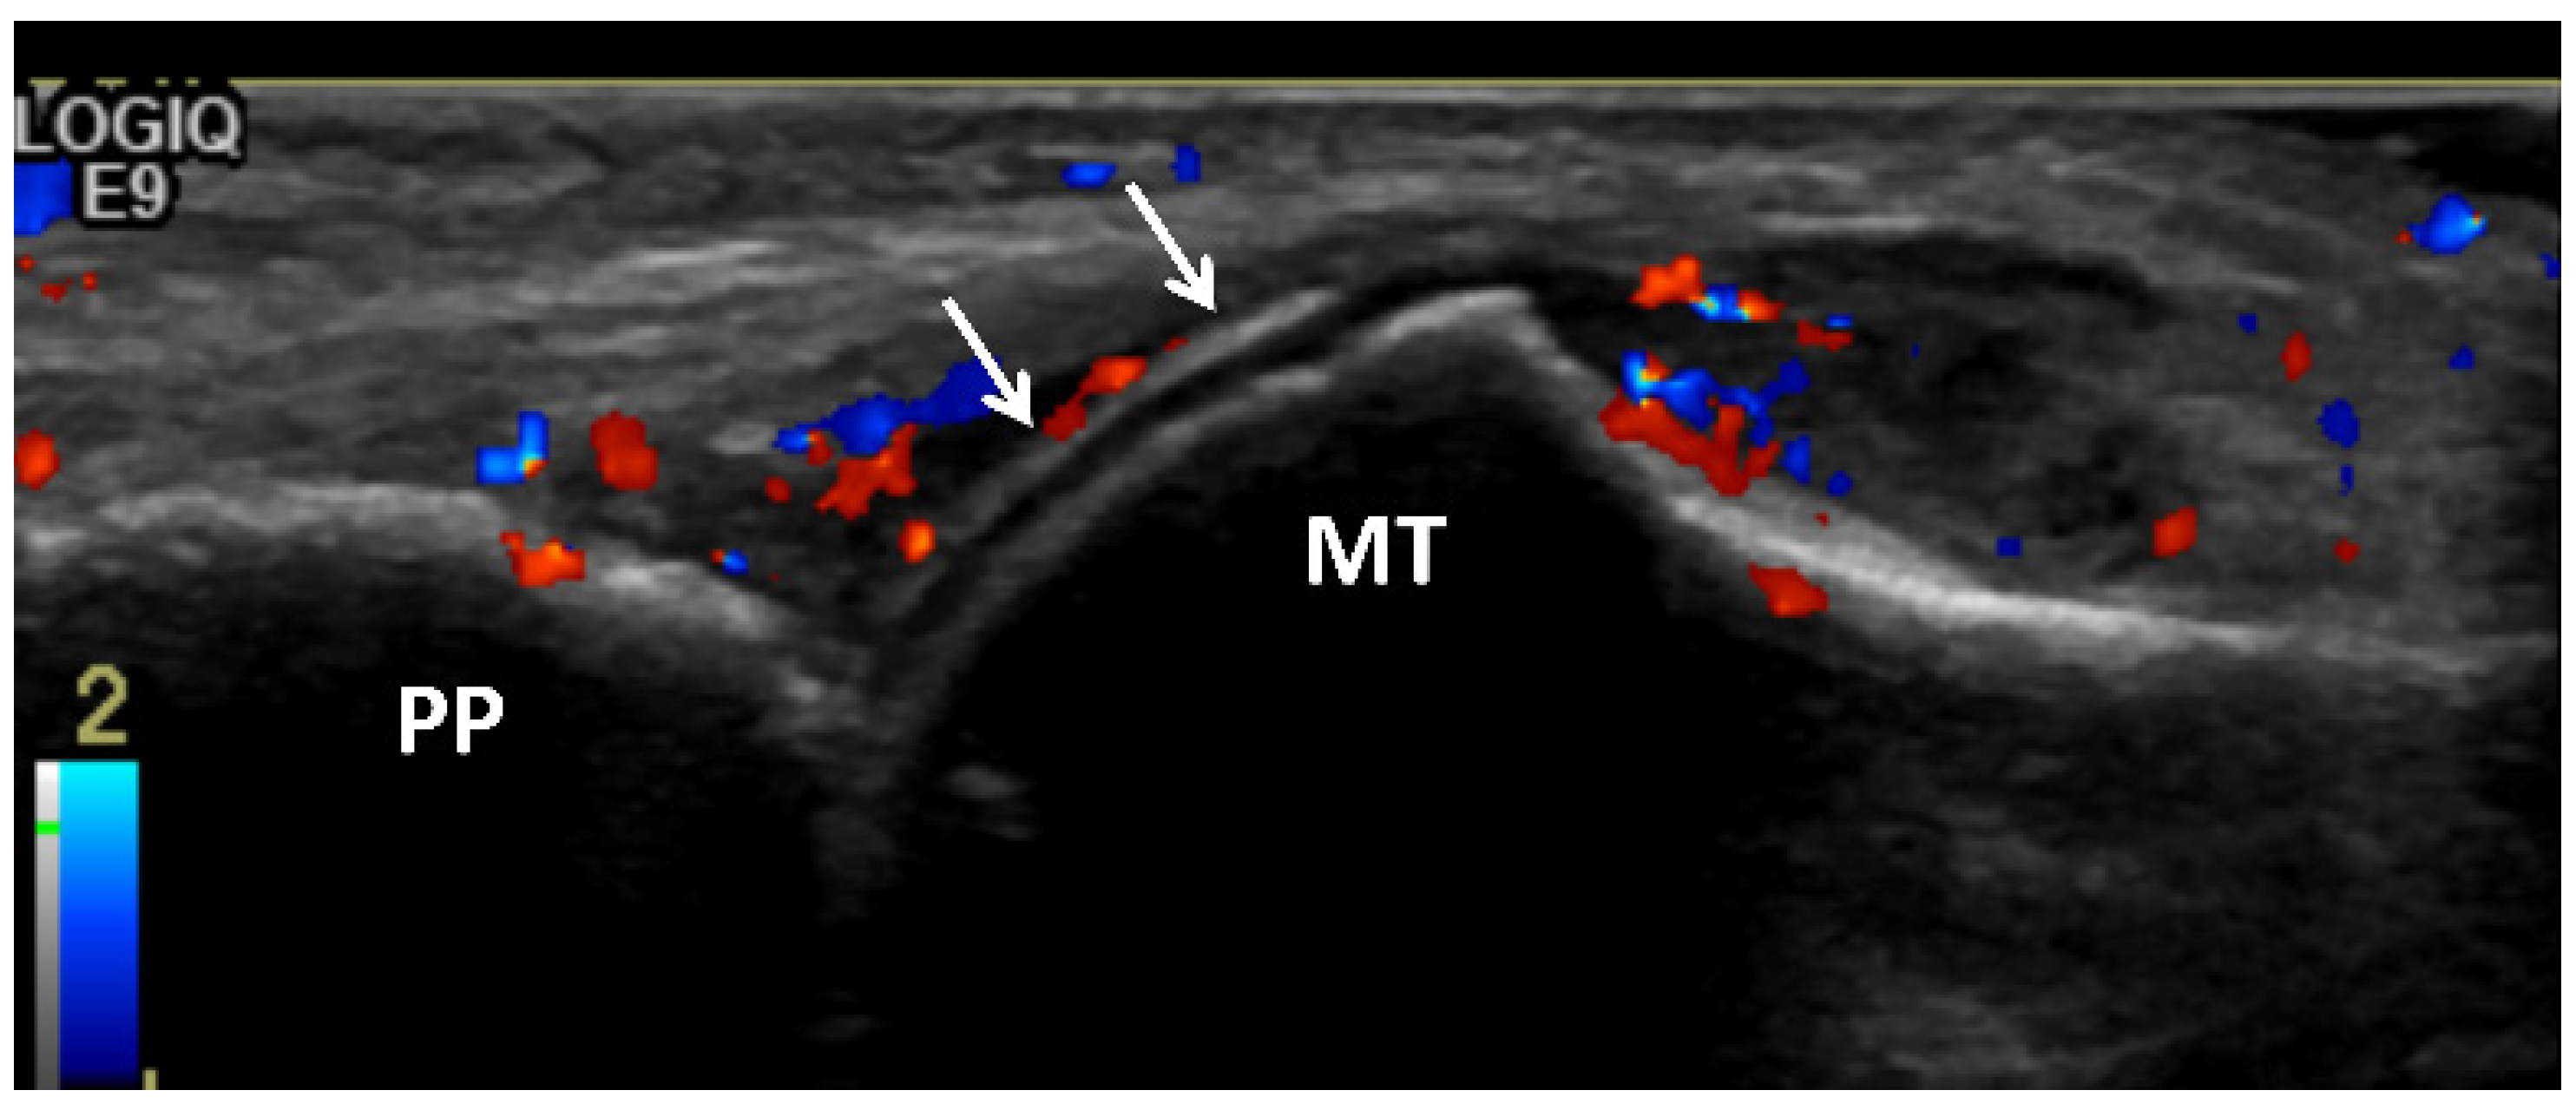

3.2. Ultrasound (US)